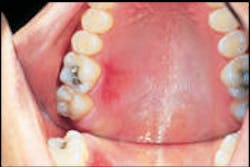

Oral examination revealed a red lesion on the hard palate of a 26-year-old male receiving routine dental treatment.

Examination of the head and neck regions revealed no unusual or significant findings. Oral examination revealed one superficial erosion on the palatal mucosa adjacent to molars. The lesion measured approximately two centimeters by one centimeter in diameter (see photo). The lesion appeared red in color. Further oral examination revealed no other oral lesions present.